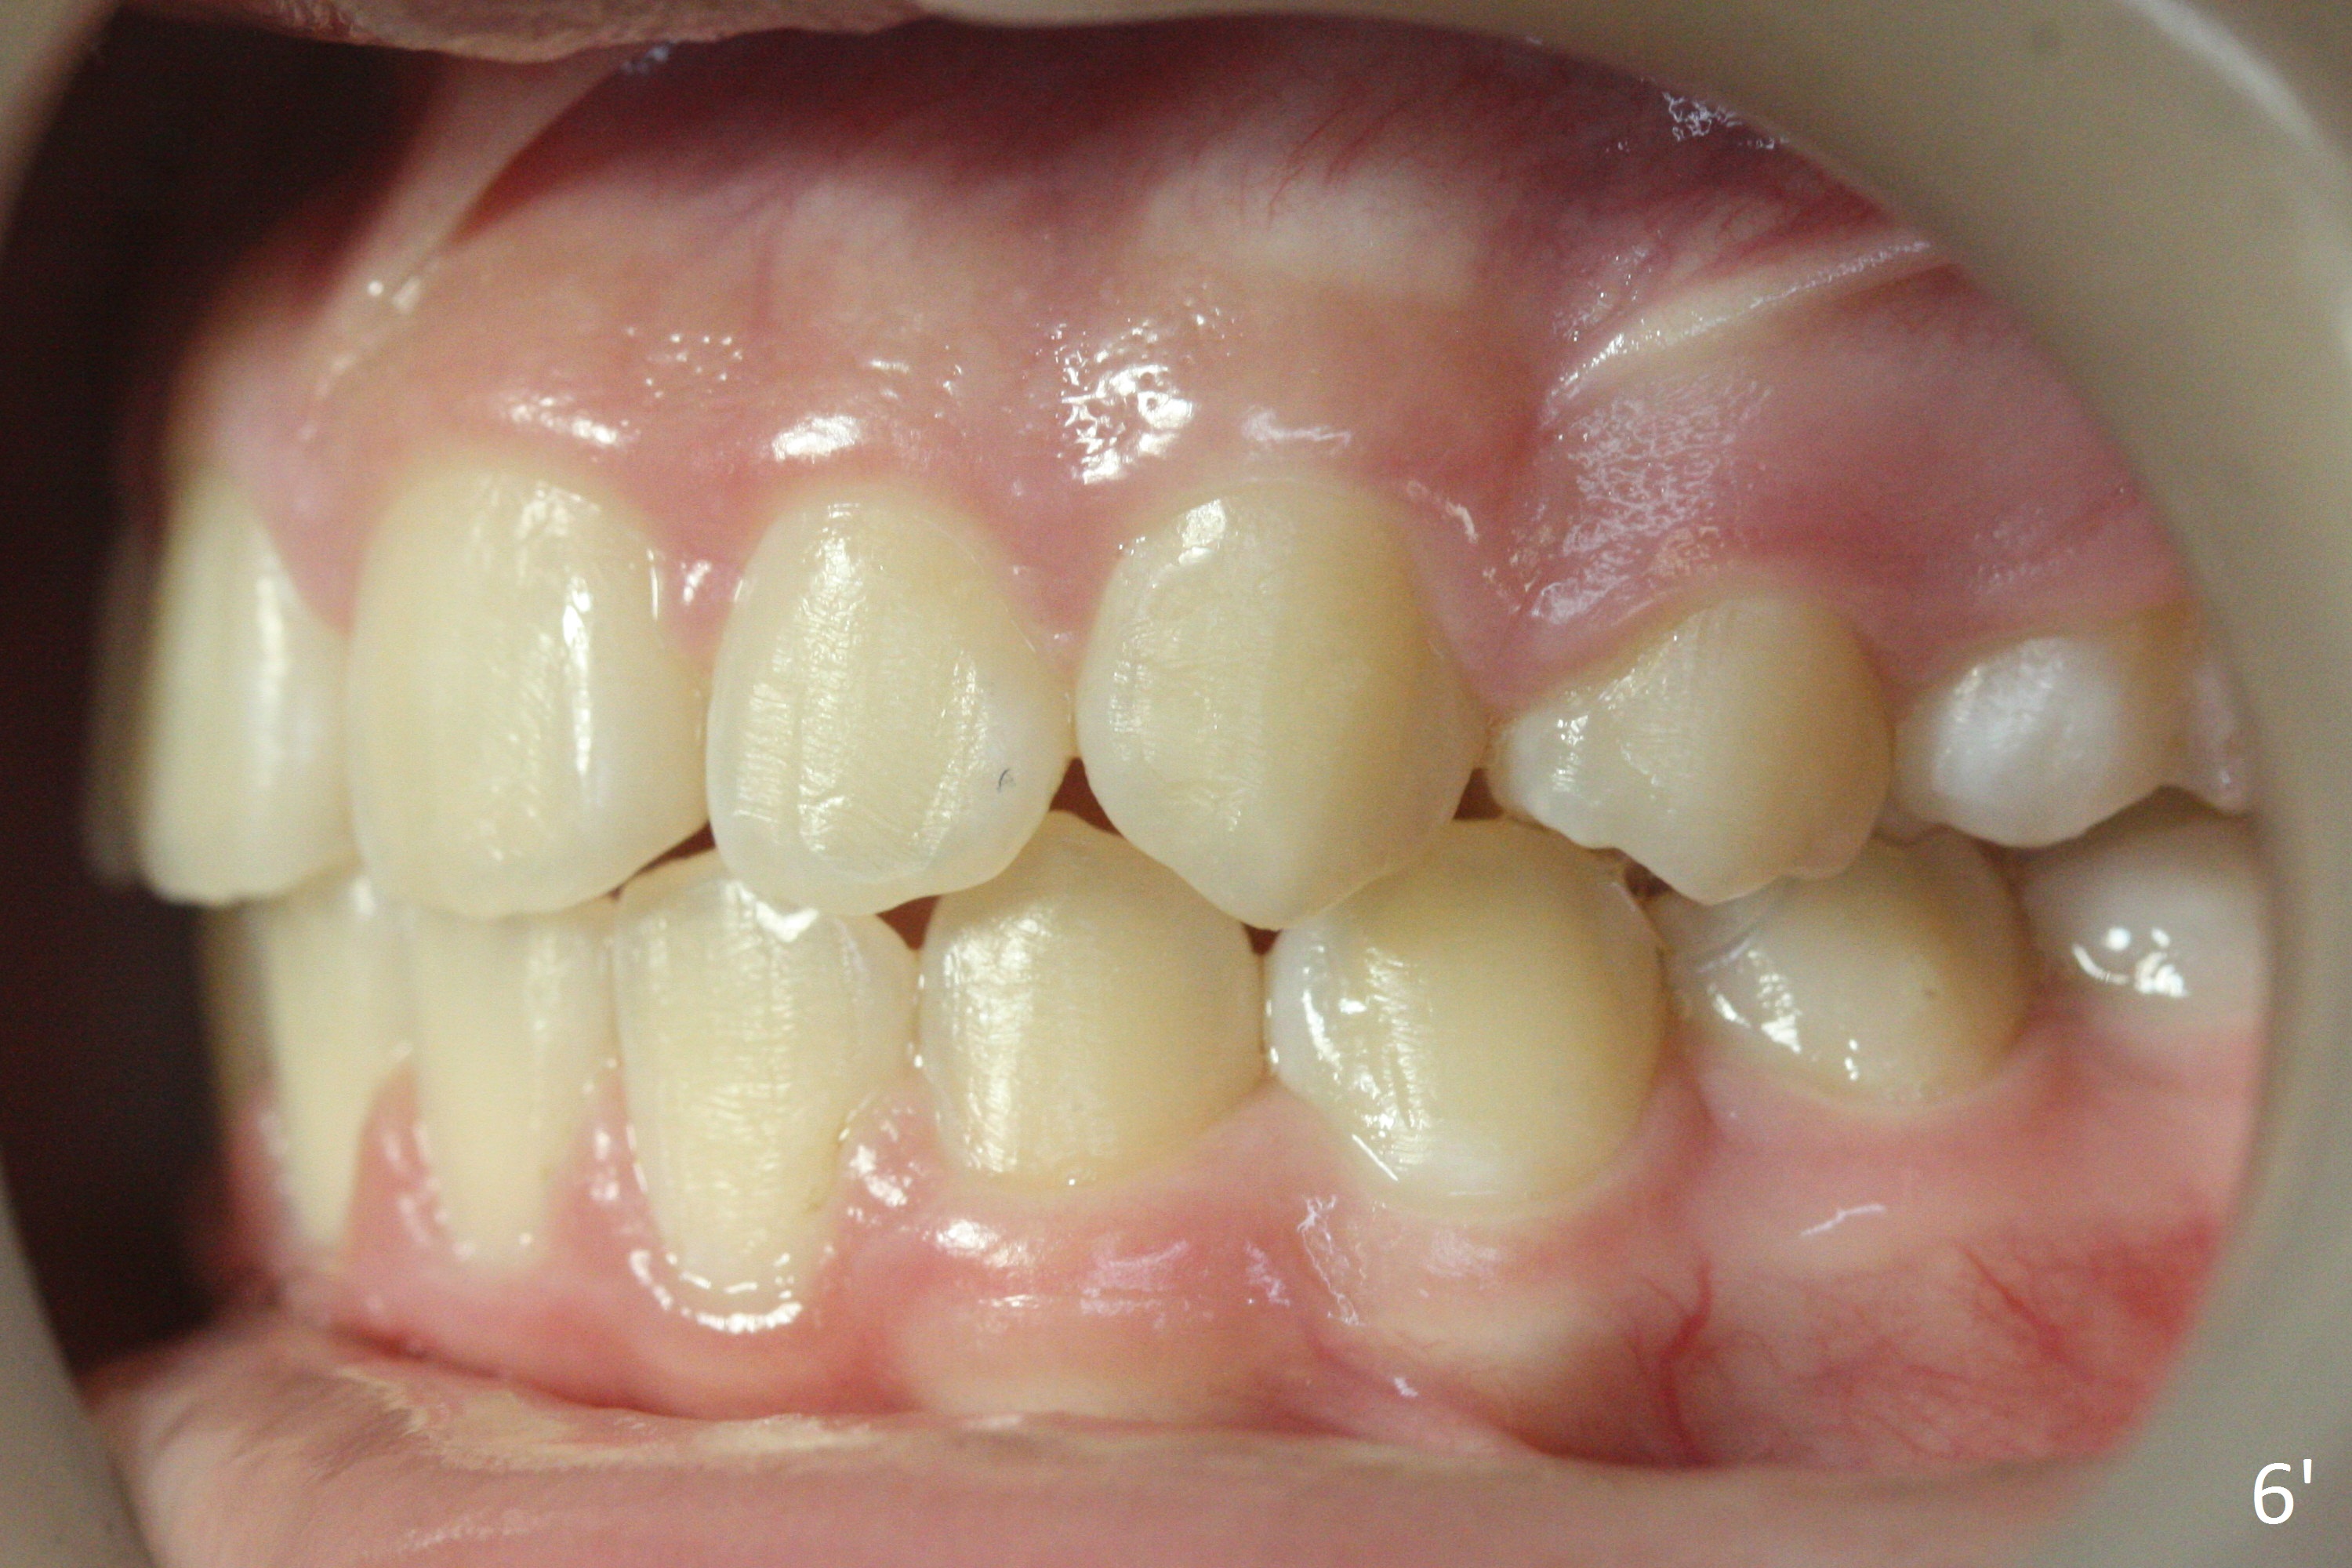

A 12-year-old girl has Class II Division I malocclusion (Fig.5,6) with protrusion of the upper lip (Fig.3). With extraction of the upper 1st bicuspids, postop facial profile improves (Fig.3', 4').

Retract the cheek retractor as posterior as possible when taking the lateral occlusal view (Fig.6,6'). Show interdigitation. Take a few of straight shots in addition to slanted ones (Fig.6).